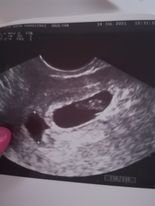

Симптомите на бременността могат да включват забавяне на менструацията, положителни тестове за бременност, кървене, коремна болка, чувствителност на гърдите, гадене и умора. Обикновено се препоръчва посещение при лекар след 10 дни закъснение или при стойности на хормона ЧХГ над 1000. В случай на кървене или други притеснителни симптоми е важно да се консултирате с лекар.